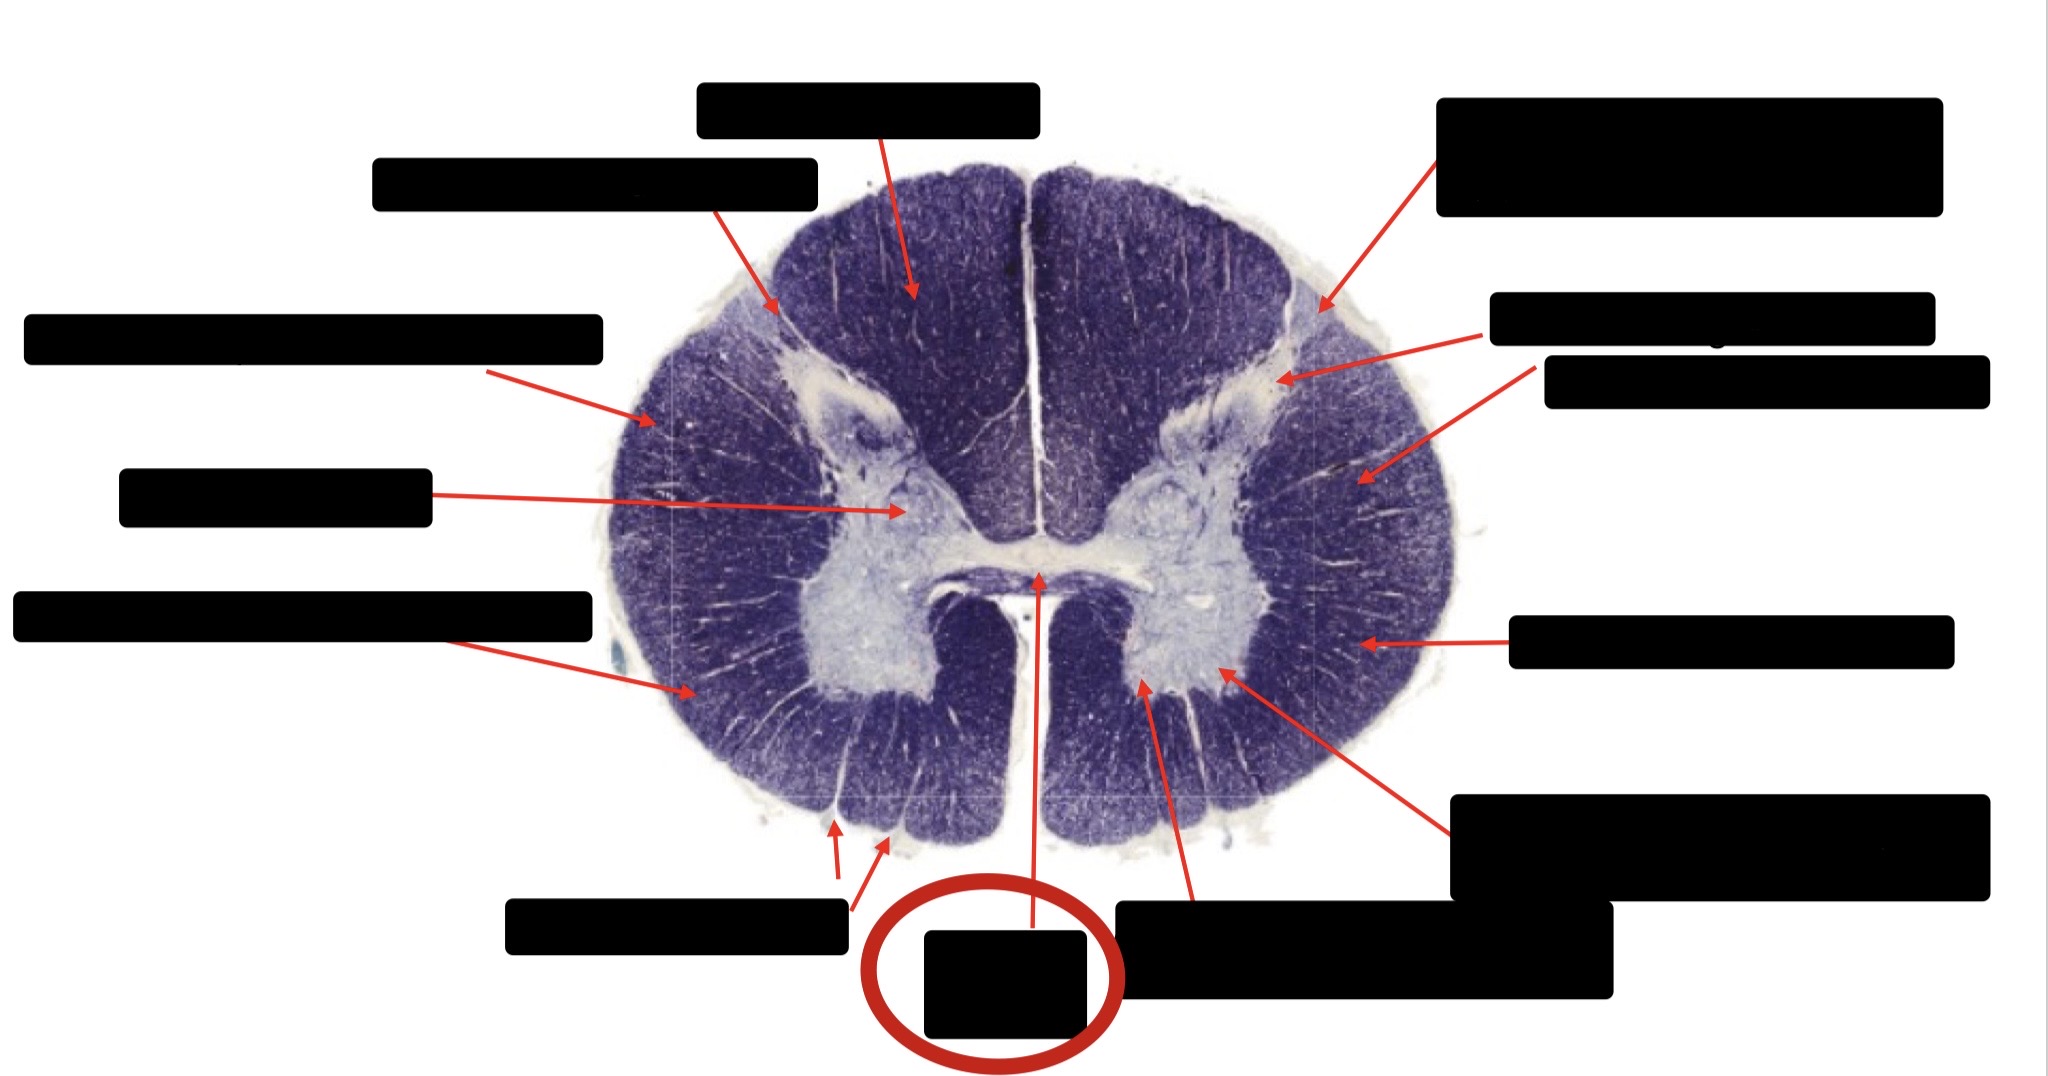

Posterior Column

Large Fiber Entry Zone

Posterior Spinocerebellar Tract

Clarke’s Nucleus

Anterior Spinocerebellar Tract

Ventral Root Fibers

Central Canal

Lissauer’s Tract & Small Fiber Entry Zone

Substantia Gelatinosa

Lateral Corticospinal Tract

Spinothalamic Tract

Anterior Horn Motor Neurons (Distal Muscles)

Anterior Horn Motor Neurons (Proximal Muscles)

Dorsal Rootlet

Lateral Horn